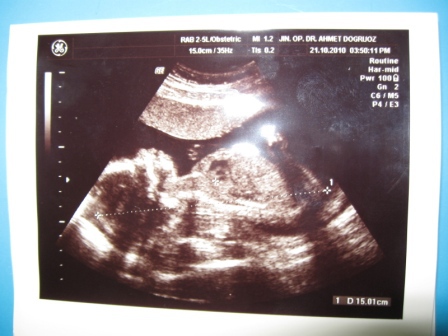

22 недели

25 неделя

19 недельВсем привет!

Я уже несколько месяцев нахожусь на нашем любимом сайте,а в дневник написать все как то не судьба была)) Живу я в Турции, в городе Измит, в 40 мин на машине от Стамбула. Сейчас мы все в ожидании нашей доченьки Мелиссы, которая должна появится в первой половине марта!))УРА!!!

Беременность моя протекает хорошо, все в порядке все в норме, малышка развивается, шевелится, пинается, с папой общается путем ответных толчков, а он радуется как ребенок!